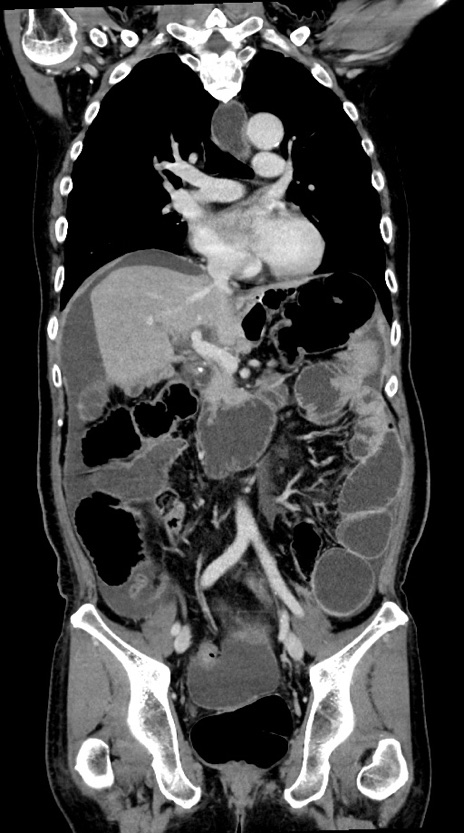

横断像

【症例】60歳代男性

【主訴】嘔吐

【現病歴】胃癌にて胃全摘後。食思不振が悪化し、夜中に嘔吐することがある。

【既往歴】胃癌、胃全摘、脾摘、胆摘後

【データ】WBC 5900、CRP 10.56